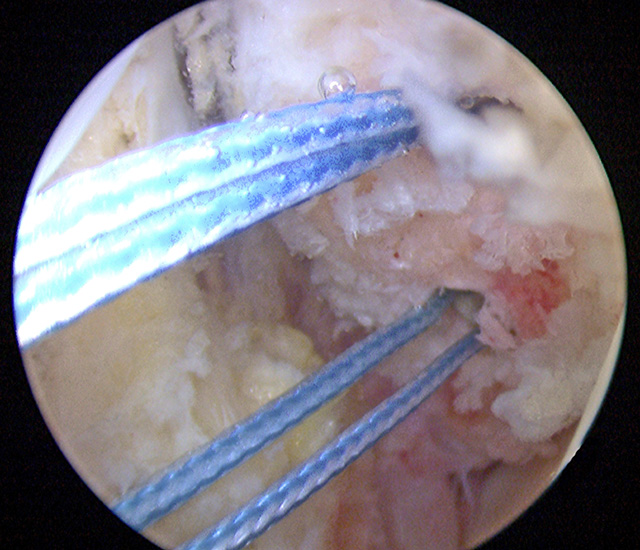

Nachfolgend wird die OP-Technik an einem rechten Sprunggelenk unter Verwendung von PEEK-Ankern veranschaulicht.

Intra- und extraartikuläre Darstellung des Operationsablaufs am linken Sprunggelenk mit selbstschneidenden Titanfadenankern.